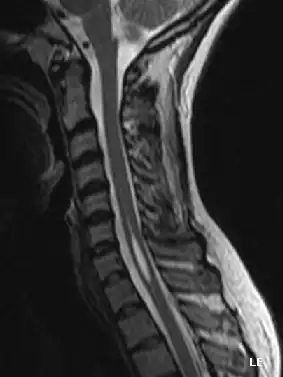

![]() Quiste dentro de la médula espinal. | ||

La siringomielia es un trastorno en el cual se forma un quiste dentro de la médula espinal. Este quiste se conoce como siringe o syrinx. Con el tiempo, el syrinx se expande y alarga, destruyendo el centro de la médula espinal. Puesto que la médula espinal conecta el cerebro con los nervios de las extremidades, este daño causa dolores, debilidad y rigidez en la espalda, los hombros, los brazos o las piernas. Otros síntomas pueden incluir dolores de cabeza (cefalea) y pérdida de la capacidad de sentir calor o frío extremos, especialmente en las manos. Cada paciente tiene una combinación distinta de síntomas.